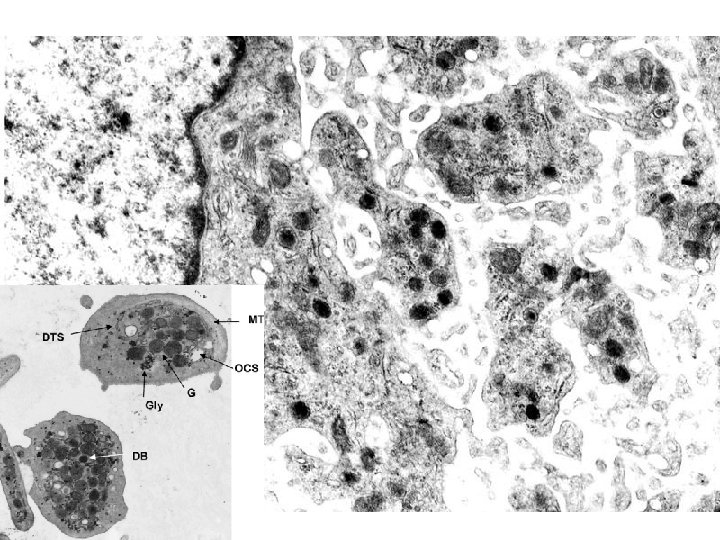

PLATELETS • ALPHA GRANULES – Fibrinogen – Fibronectin – Factor-V, Factor-VIII – Platelet factor 4, TGF-beta • DELTA GRANULES (DENSE BODIES) – ADP/ATP, Ca+, Histamine, Serotonin, Epineph. • With endothelium, form TISSUE FACTOR

NORMAL platelet on LEFT, “DEGRANULATING” ALPHA GRANULE ON RIGHT AT OPEN WHITE ARROW

PLATELET PHASES • ADHESION • SECRETION (i. e. , “release” or “activation” or “degranulation”) • AGGREGATION